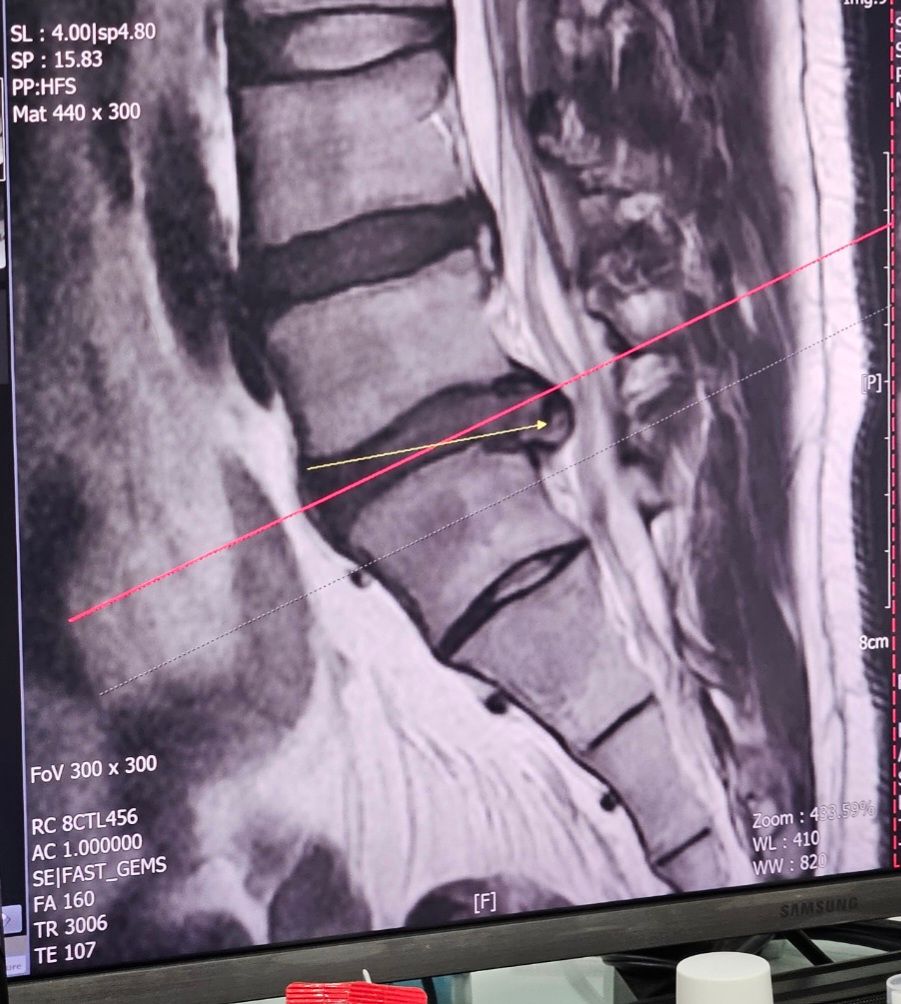

제가 최근에 5번 6번 척추에 허리디스크가 생겼는데요.

※ 제 허리디스크 사진이랑 자세교정기 사진 첨부합니다. ※

• 1번 째 사진